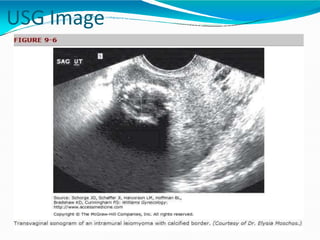

Imaging

Sonography is the most readily

available and least costly to

differentiate fibroids from other

pelvic pathology . It is reasonably

reliable forevaluation of uterus with

< 375 ccvolumeand 3-4 or fewer

fibroids.

USG Image